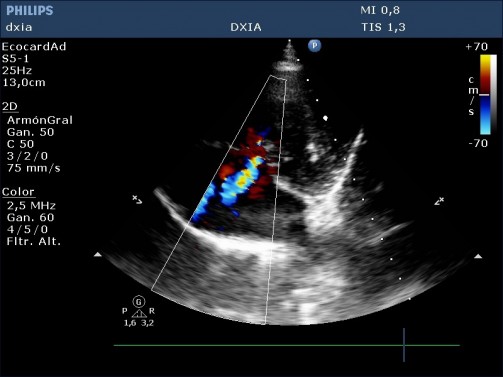

Insuficiencia tricuspídea excéntrica de alta velocidad (4,2 m/seg)

Arteria pulmonar dilatada pero perfil flujo pulmonar debido a:

- Conducto arterioso persistente, aunque no se visualiza, no puede descartarse completamente. Habría que realizar una prueba de contraste.

- Hipertensión primaria congénita por retención de características fetales en la circulación pulmonar.